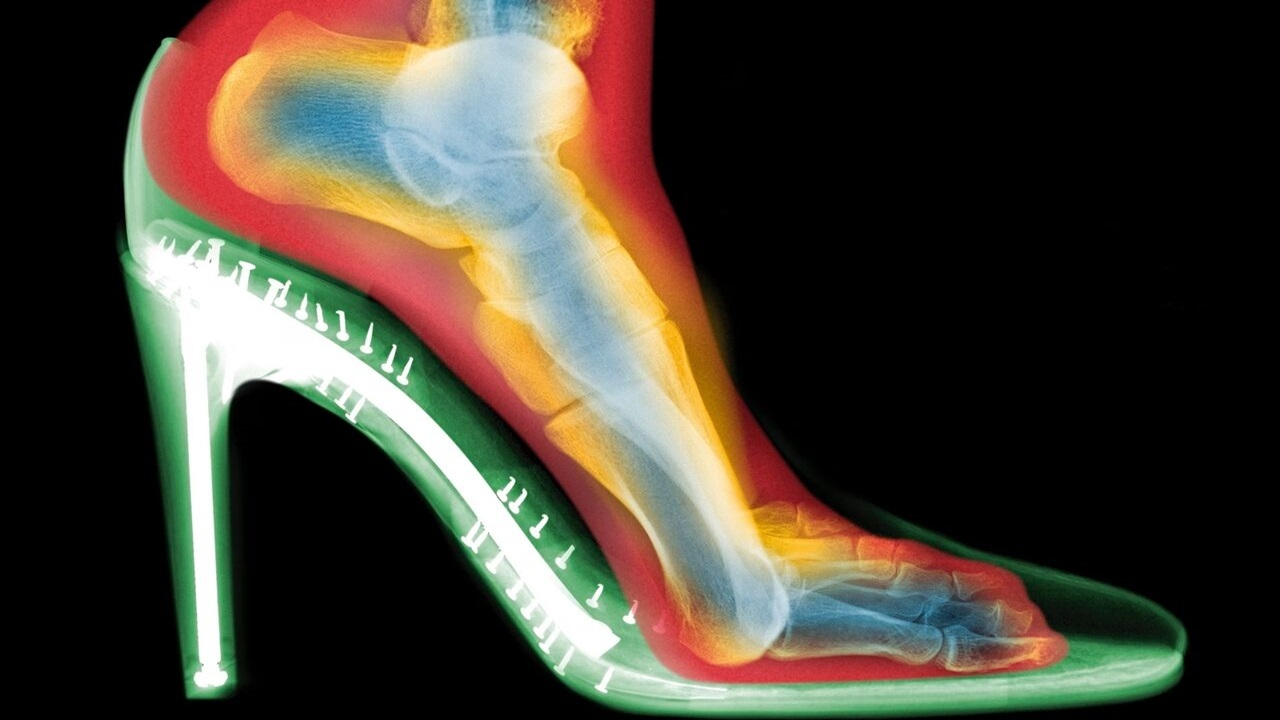

گلدبرگ دو اسکن از پای یک فرد تهیه کرد: یکی بدون کفش و دیگری با کفش پاشنهبلند. تفاوتها چشمگیر بود:

فشردگی انگشتان: انگشتان پا در کفش به هم فشرده شده بودند؛

انحراف شست پا (بونیون): مفصل انگشت شست به طرف بیرون متمایل شده بود؛

انگشتان چنگالی: انگشتان کوچکتر برای حفظ تعادل، حالتی قفلشده و خمیده به خود گرفته بودند.